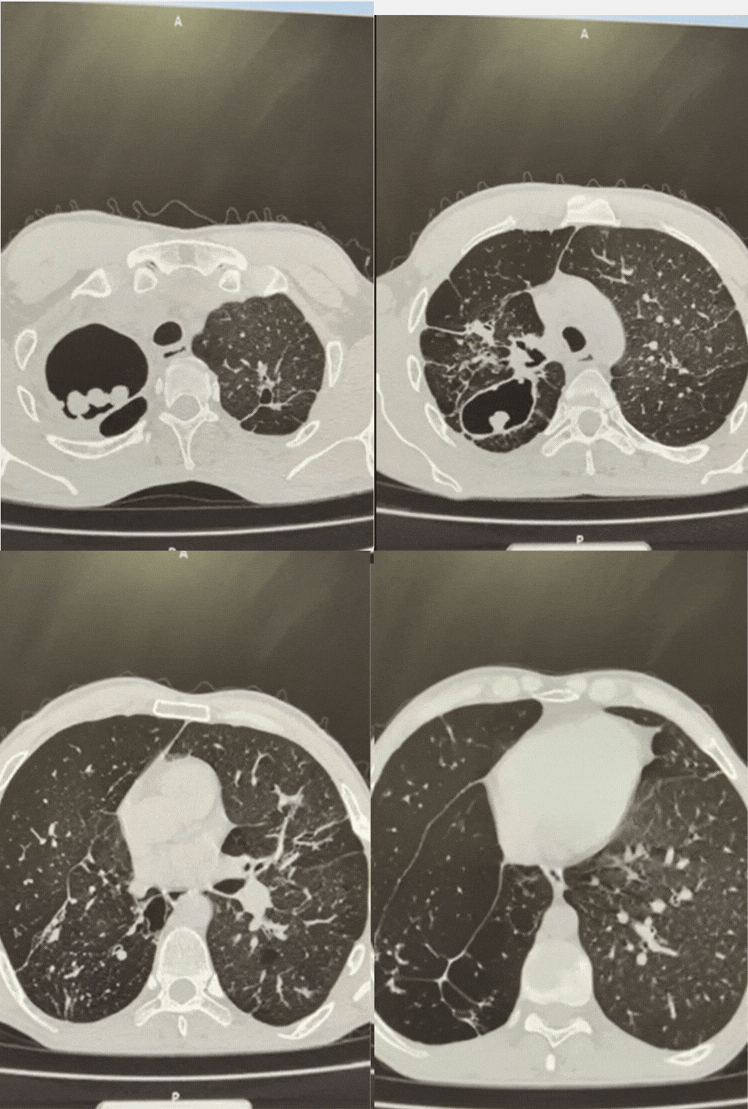

All patients were discharged in satisfactory condition (Figures 1 and 2). At long-term follow-up (1 to 11 years), all patients are alive, and no recurrence of aspergillosis was noted (Figure 3).

Figure 1: Observation No. 5 before surgery.

Figure 2: Observation No. 5 one year after surgery.